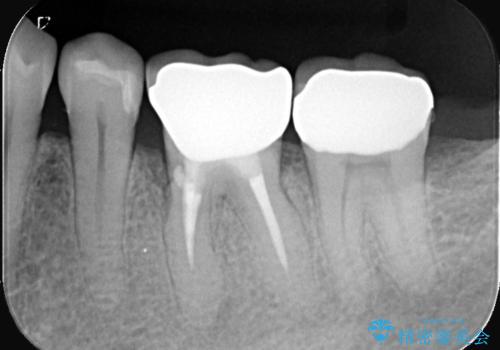

- お口の中にある銀歯を全てなくして、白く健康的な状態にしたい」という主訴でご来院されました。長年使用してきた複数の銀歯は、経年劣化により適合が悪くなっており、一部では内部で二次カリエス(虫歯の再発)も認められました。

患者様と相談の上、全ての金属(メタル)を取り除き、生体親和性が高く審美性に優れた素材へ置き換えるメタルフリー治療の計画を立案。部位や欠損の大きさに合わせ、セラミックインレーおよびセラミッククラウンを用いて、お口全体の調和を整えることとしました。

銀歯の除去と精密な再治療: 古い銀歯を一つひとつ丁寧に取り外し、内部の虫歯を徹底的に除去。神経を保護するための処置を行った上で、適合性を極限まで高めるために精密な型取りを行いました。

オールセラミックによる修復: 天然歯のような光の透過性と硬さを持つオールセラミックを使用しました。奥歯であっても、患者様固有の歯の色調や咬み合わせの溝を忠実に再現した修復物を装着。金属を一切使用しないことで、金属アレルギーのリスクを排除し、歯肉の色が黒ずむ心配もなくなりました。